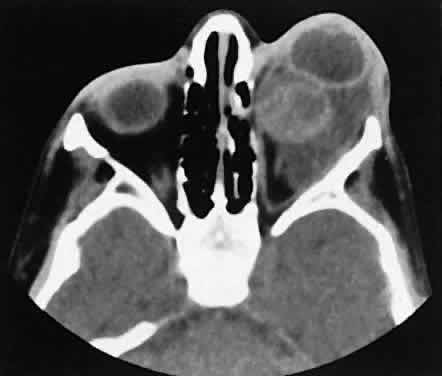

| The orbital manifestations of a vascular process are dependent on whether

the lesion is on the venous or the arterial circulation. Patients with

venous lesions (varix) characteristically report a history of intermittent

proptosis with either a Valsalva's-type maneuver or having

the head in a dependent position. Suspicion of a venous varix should

alert the radiologist to perform the scan before and after a Valsalva's

maneuver.9,10 Color flow doppler imaging showing reversal of flow during a Valsalva

maneuver also is a helpful finding. Phleboliths may or may not be present. Another

clue to the diagnosis of a varix is the location, many times

in the posterior, inferior lateral orbit, seemingly coming out of

the inferior orbital fissure near the apex. Lesions that appear to change

size or shape from the axial view to the coronal view also have turned

out to represent a varix based on our experience (Fig. 2). Arterial lesions may either have high or low flow. The high-flow lesions are carotid cavernous sinus fistulas and result from a direct communication between the carotid artery and the cavernous sinus. These arise spontaneously or as a result of trauma. The orbit is involved as an innocent bystander, because all signs and symptoms of orbital involvement follow from the retrograde transmission of increased venous pressure from the cavernous sinus. EOMs generally are enlarged, as is the SOV. The ipsilateral cavernous sinus also is enlarged. Intercommunication between the cavernous sinuses also may account for the occasional bilateral findings. Low-flow lesions result from increased blood flow through the cavernous sinus, but the intracavernous carotid artery itself is intact (Fig. 3). These typically are dural-cavernous sinus fistulas. A high index of suspicion may be required to diagnose these, but a fairly stereotyped presentation is a unilateral red-eyed glaucoma with proptosis. Abduction weakness also may be present. Enlargement of one or more EOMs along with an enlarged SOV are noted with CT scanning. A small lesion may escape detection with CT scanning and require high-resolution MRI or even selective internal and external carotid angiography for diagnosis if a high degree of clinical suspicion exists. In a patient with a known dural fistula, a sudden and dramatic deterioration in the clinical picture may be seen with a thrombosis of the SOV.11 The radiographic picture, at least regarding the CT appearance, probably will not change. MRI can nicely show the thrombosis in the SOV.